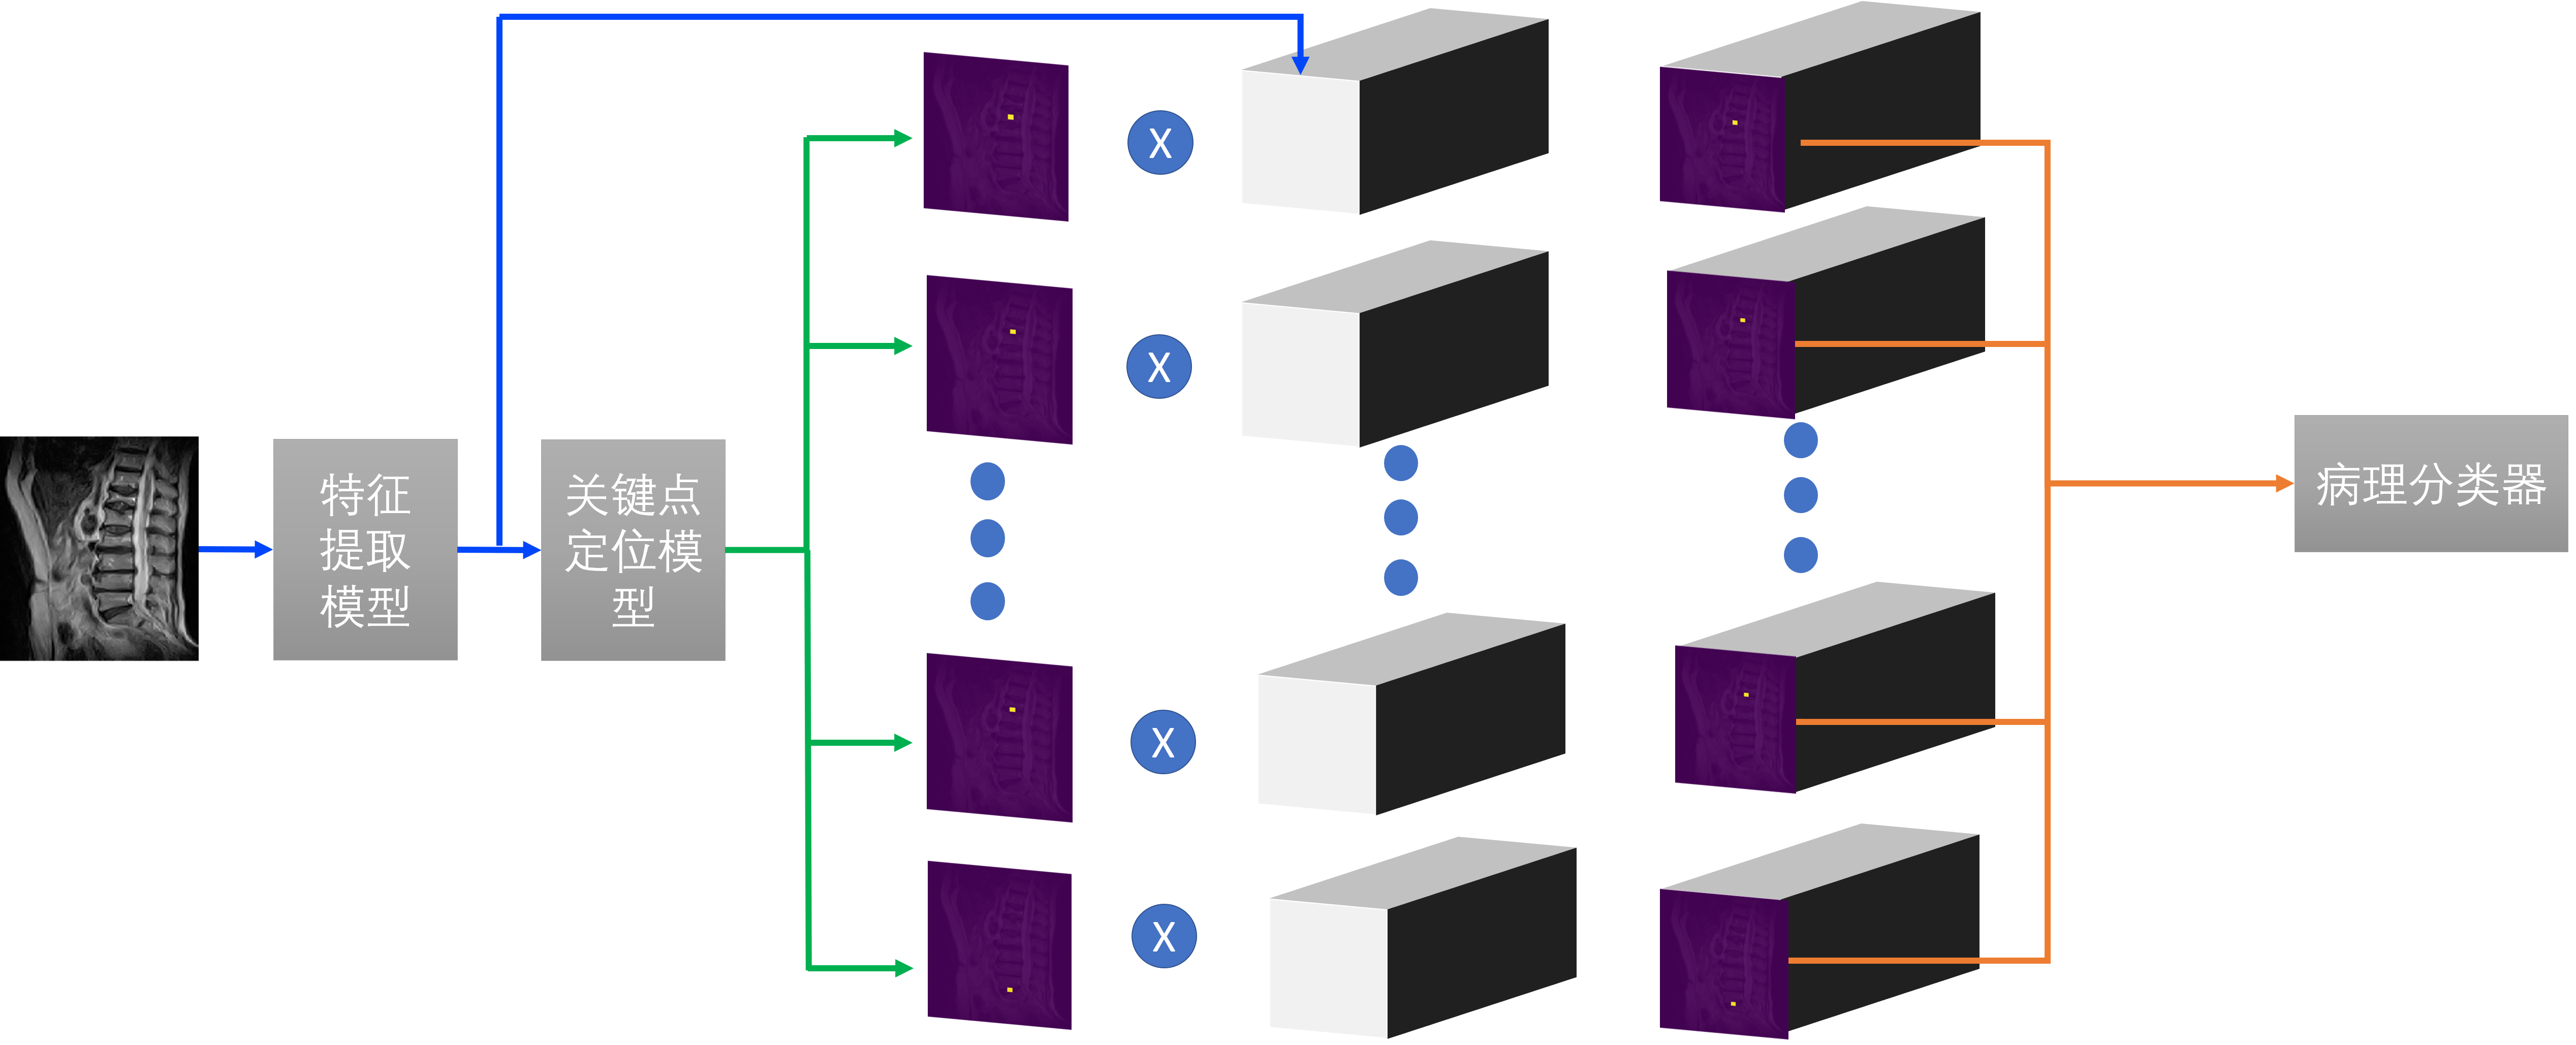

在得到腰椎关键点热力图之后,我们对每个关键点的热力图进行一个5x5的maxpool,扩大热力图关键点区域的面积。然后将每个热力图和前端模块的特征相乘,得到11个不同位置的融合后的特征图。将这些融合后的特征送入分类器中就可以得到腰椎对应的病理类别,整个过程示意图如图。